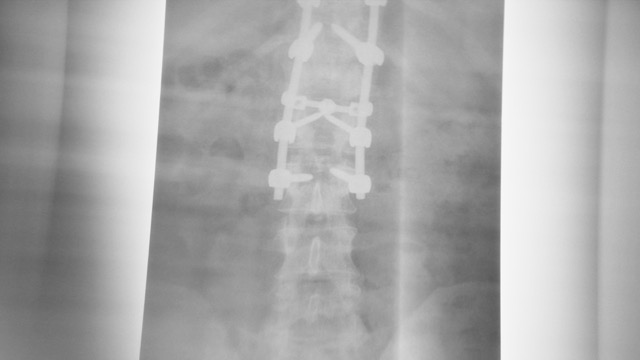

RESTORED is a documentary short film that follows Brooklyn Coachworks founder Daniel Marcello, one of America’s most sought after Land Rover Defender restoration shops. For nearly two decades, Daniel has devoted himself to preserving the spirit of the original Solihull-era Defenders, purpose-building each truck for real world use. But while traveling through Italy, Daniel survived a devastating accident that left him temporarily paralyzed. After months of recovery and relearning how to walk, he returned home with a renewed sense of purpose and a deeper bond with his machines and himself. RESTORED is a story about craftsmanship, resilience and the pursuit of freedom.

Brooklyn Coachworks founder Daniel Marcello survives a life-altering accident while traveling through Italy. After months of recovery and relearning how to walk, he returns home with a renewed purpose and a deeper connection to the Land Rovers he builds. A story about craft, resilience, and the pursuit of freedom.